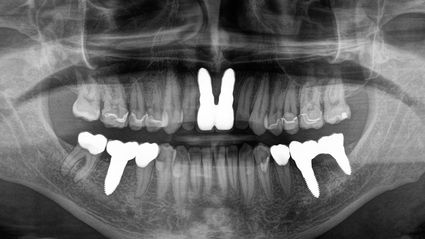

My first visit was in December 16. I had my 4 wisdom teeth cavitations cleaned, 3 more cavitations (from teeth that had been extracted in the summer 16 in the USA) cleaned, and implants placed. I also had a gold crown removed, along with a little metal. This last visit on July 16, we fixed various teeth that had plastic fillings and replaced them with ceramic fillings and crowns. We most importantly extracted 2 teeth that had deep root infections, cleaned cavitations and placed 2 implants. I experienced an almost immediate sigh of relief in my whole body. Then a boost of energy! Here, all the attention is paid to ensuring the patient has the best chance to heal and recover both before, during, and after surgery.